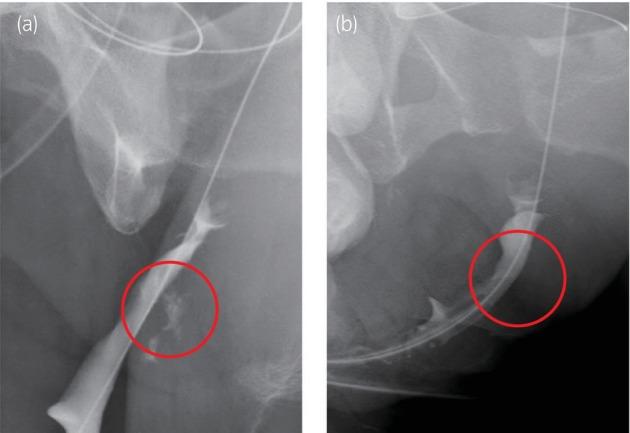

A transgender man underwent surgery at a private clinic and experienced recurrent complications. Subsequent examination at another clinic and our hospital revealed limited medical records, complicating our understanding of this case. After a detailed investigation, the urethrocutaneous and urethrovaginal fistulas were identified and addressed by joint urologists and plastic surgeons, resulting in no recurrence after 1 year.

一名跨性别男性在一家私立诊所接受手术,术后出现反复并发症。随后在另一家诊所和我院检查发现病历有限,这使我们对该病例的了解变得复杂。经过详细调查,泌尿外科医生和整形外科医生联合确定并处理了尿道皮肤瘘和尿道阴道瘘,术后1年未复发。